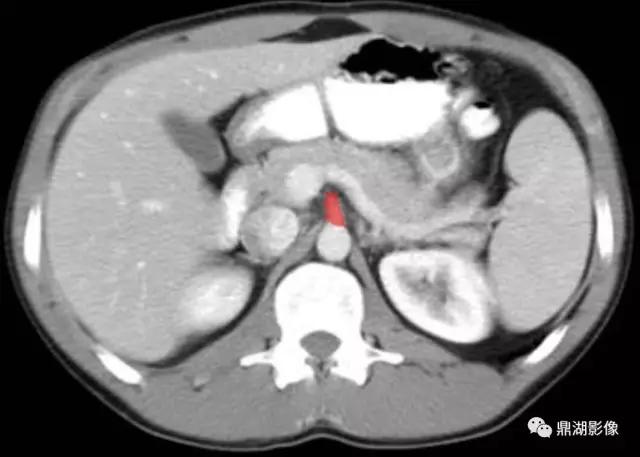

肠系膜上动脉(Superior Mesenteric Artery)

肠系膜上静脉(Superior Mesenteric Vein)